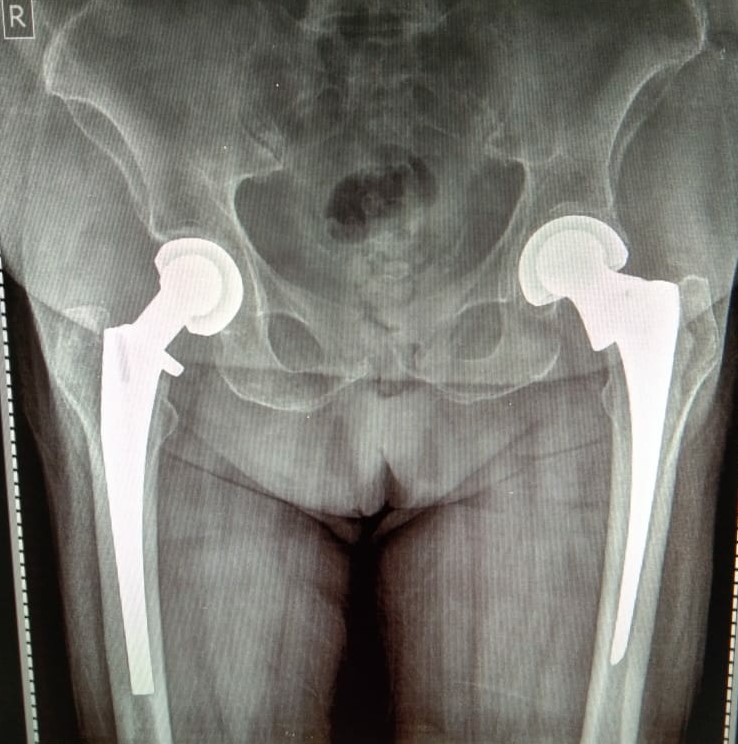

Knee and Hip Replacement